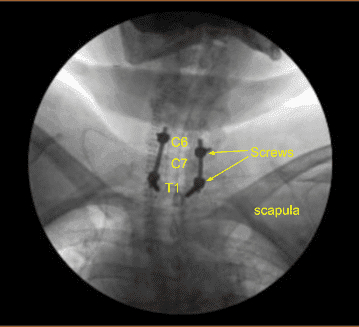

Se utilizó un marco estereotáctico guiado por imagen con técnicas de neuronavegación para colocar la instrumentación. Colocamos tornillos pediculares bilaterales T1 y decorticamos con canulación eléctrica de alta velocidad con el localizador pedicular de mano, palpando para detectar brechas, midiendo las profundidades, subroscando 11 mm y colocando tornillos pediculares de titanio de 30 mm x 5,0 mm bilateralmente sin dificultad.

Los potenciales evocados motores se comprobaban periódicamente y eran estables. A continuación, cenulamos las masas laterales bilaterales de C5 y C6 utilizando técnicas de navegación, decorticando con un taladro eléctrico de alta velocidad, canulando con una guía de perforación de 12 mm y un taladro eléctrico de mano, palpando en busca de brechas, y rellenando el agujero con Surgiflo.

A continuación, colocamos tornillos bilaterales de masa lateral en C6. Al inspeccionar la deformidad de la columna, se decidió no colocar los tornillos de masa lateral C5 debido a la deformidad cifótica y la dificultad para colocar las varillas.

Así que luego decoricamos las articulaciones en C6-C7 y C7-T1 y los procesos transversales bilaterales T1 con un taladro eléctrico de alta velocidad para la artrodesis. El autoinjerto resecado fue fragmentado. Se colocaron varillas de titanio precortadas y predelineadas sobre los tulipanes desde C6 hasta T1, se aseguraron con tapones de bloqueo y luego se apretaron finalmente con un dispositivo de par y antitorque.